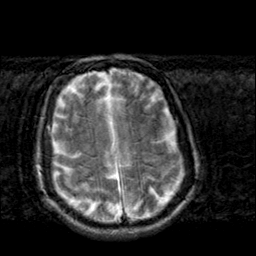

Creutzfeld-Jakob disease: T2-weighted MR -- Slice #17

[Home][Help][Clinical] Slice 17